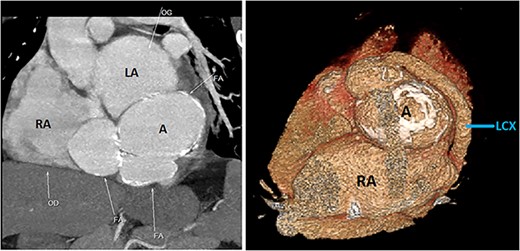

Initial physical examination showed stable vital signs. Auscultation found systolic murmurs of mitral and tricuspid regurgitations. There were no peripheral edema or other signs of heart failure. Abdominal examination revealed no tenderness, hepatomegaly or ascites. Electrocardiogram at admission showed sinus rhythm with no conduction abnormalities or signs of ischemia. Chest radiograph found an enlargement of the cardiac silhouette. Routine blood tests were normal. Transthoracic echocardiography (TTE) found a bi-atrial cystic structure, which we initially suspected to be a hydatid cyst as cystic echinococcosis is highly endemic in Morocco. Color Doppler showed a massive shunt with blood coming into the right atrium (RA) from an unknown source (Fig. 1). Cardiac magnetic resonance imaging (CMR) showed a bilobed cystic lesion hypointense on T1 and T2 sequences, with the same signal as cardiac chambers, located below and behind the left atrium (LA). The superior lobe was 48-mm wide and the inferior lobe 65-mm wide. On the peripheral wall of this structure, a giant circumflex artery (LCX), with a right atrial shunt, was present (Fig. 2). Coronary angiography (CA) along with computed tomography angiography (CCTA) confirmed the bilobed circumflex saccular aneurysm and CAF (Figs 3 and 4).

CCTA (with 3D reconstruction) showing the CAF alongside a bilobed saccular aneurysm fed by a giant circumflex artery, next to the RA. A, aneurysm of the circumflex artery; LCX, circumflex artery.